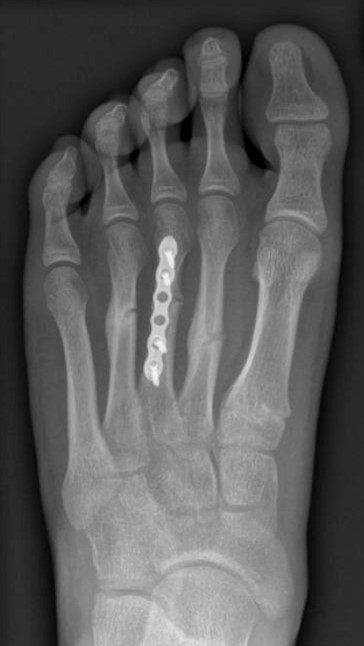

Case 1 - Pedestrian hit by car

Figure 3: 3 months post fixation